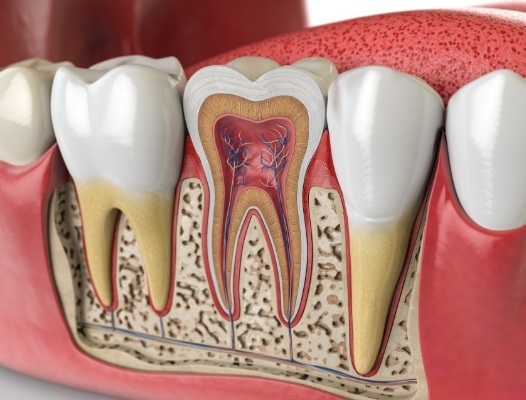

To understand how a tooth can become infected in the first place, we first need to examine the structure of a tooth. Each tooth consists of three layers. The outermost layer is called enamel. This extremely hard surface gives your smile an attractive sheen.

Below the enamel is dentin, a somewhat softer and slightly porous material. At the center of each tooth is the pulp chamber. Here, blood, lymph and nerve tissue transport nutrients to the tooth and remove waste through root canals that connect to your bloodstream.

Normally, the chamber and canals are protected by the enamel and dentin. However, if you have a large cavity, a crack or a loose filling, then bacteria can migrate to the interior. When this happens, infection can begin.

After the tooth and surrounding tissue are anesthetized, your dentist accesses the pulp chamber and root canals through a small hole. Using special instruments, the infected portion of the tooth is removed. Then, the space is disinfected and filled with a biocompatible substance that expands to fill the chamber and root canals. This supports the remaining tooth structure and prevents recontamination. Finally, the tooth is sealed and prepared for a porcelain crown that will protect your tooth.